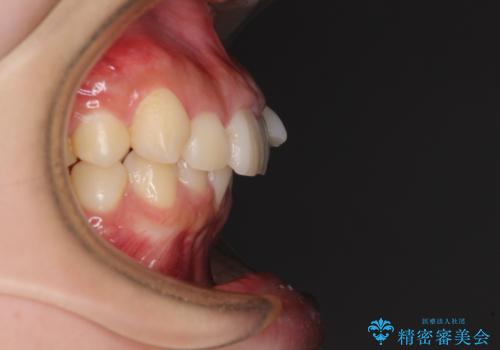

下顎前歯が隠れて突出した口元 ワイヤー装置での抜歯矯正

- 前歯のデコボコと口元の突出感を気にして来院された患者様です。

下顎骨の左右差や、上顎骨の前方位などが認められたため、上下左右の第1小臼歯4本を抜歯し、ワイヤー装置にて矯正治療を行うこととしました。

骨格的な左右差がありましたが、何とか当初予定していた期間で、左右対称の咬み合わせに仕上げることができました。